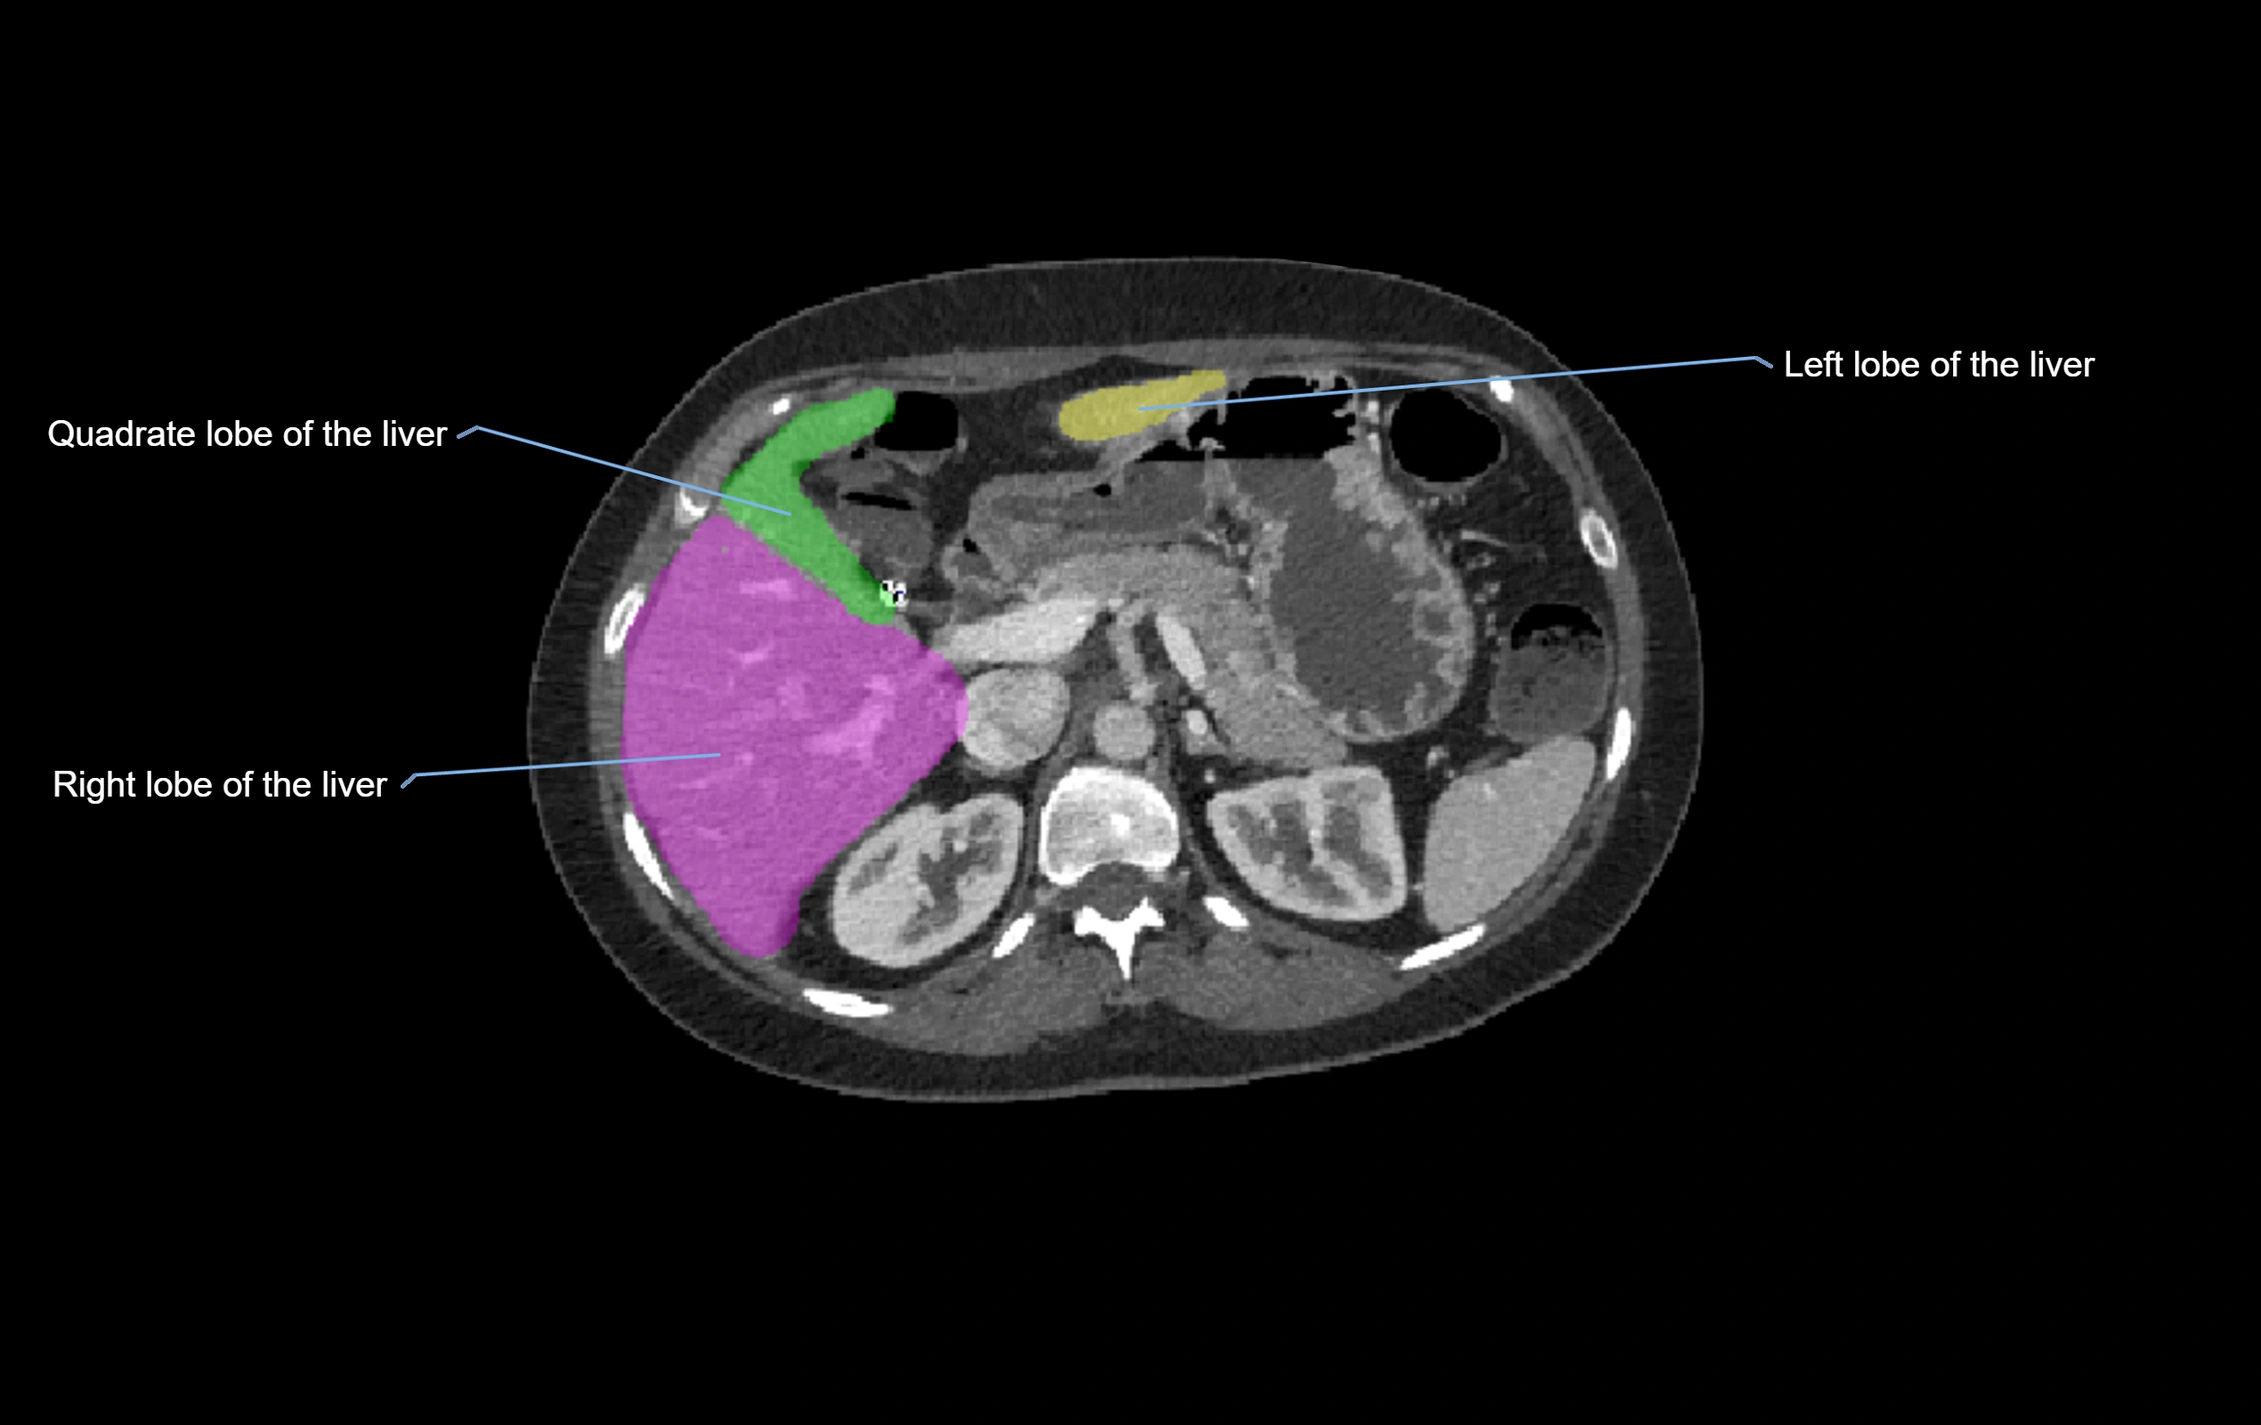

CT Image

image